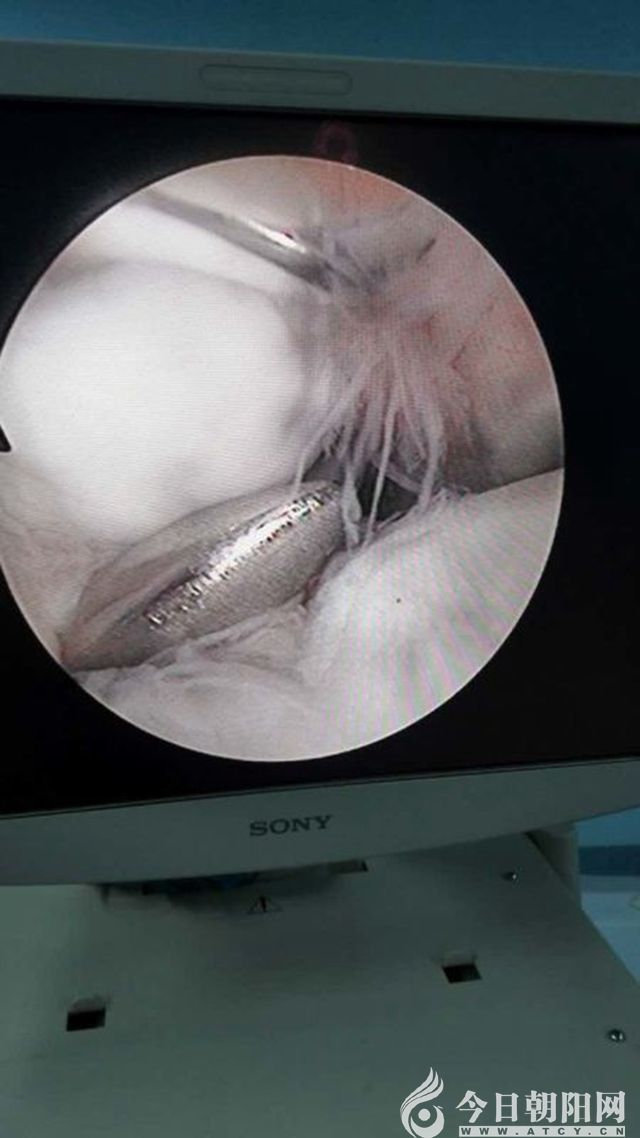

近日,朝陽市第二醫(yī)院骨外科(一)病房成功實施一例肘關(guān)節(jié)鏡手術(shù),為患者取出了肘關(guān)節(jié)內(nèi)的游離體,解除了患者的病痛。目前,患者肘關(guān)節(jié)功能恢復(fù)良好,已痊愈出院。據(jù)悉,此例手術(shù)在朝陽地區(qū)尚屬首例。

患者男性,18歲,10年前出現(xiàn)右肘關(guān)節(jié)疼痛,并逐漸出現(xiàn)右肘關(guān)節(jié)活動受限、卡阻現(xiàn)象,患者為此苦不堪言。在輾轉(zhuǎn)多家醫(yī)院后,慕名來到市二院骨外科就診,骨外科(一)病房副主任、主任醫(yī)師徐剛結(jié)合其病史,完善相關(guān)檢查后,診斷為右肘關(guān)節(jié)骨性關(guān)節(jié)炎,右肘關(guān)節(jié)游離體。決定采用關(guān)節(jié)外科領(lǐng)域的新技術(shù)——肘關(guān)節(jié)鏡微創(chuàng)技術(shù)對該患者實行手術(shù)治療。經(jīng)過細(xì)致周密的術(shù)前準(zhǔn)備,為患者成功實施了肘關(guān)節(jié)鏡微創(chuàng)手術(shù),手術(shù)歷時50分鐘,切口只有5mm左右,于肘關(guān)節(jié)內(nèi)順利取出一枚1.0*1.5cm大小的游離體。術(shù)后,患者肘關(guān)節(jié)疼痛及卡阻現(xiàn)象消失,屈伸活動良好,目前已痊愈出院。